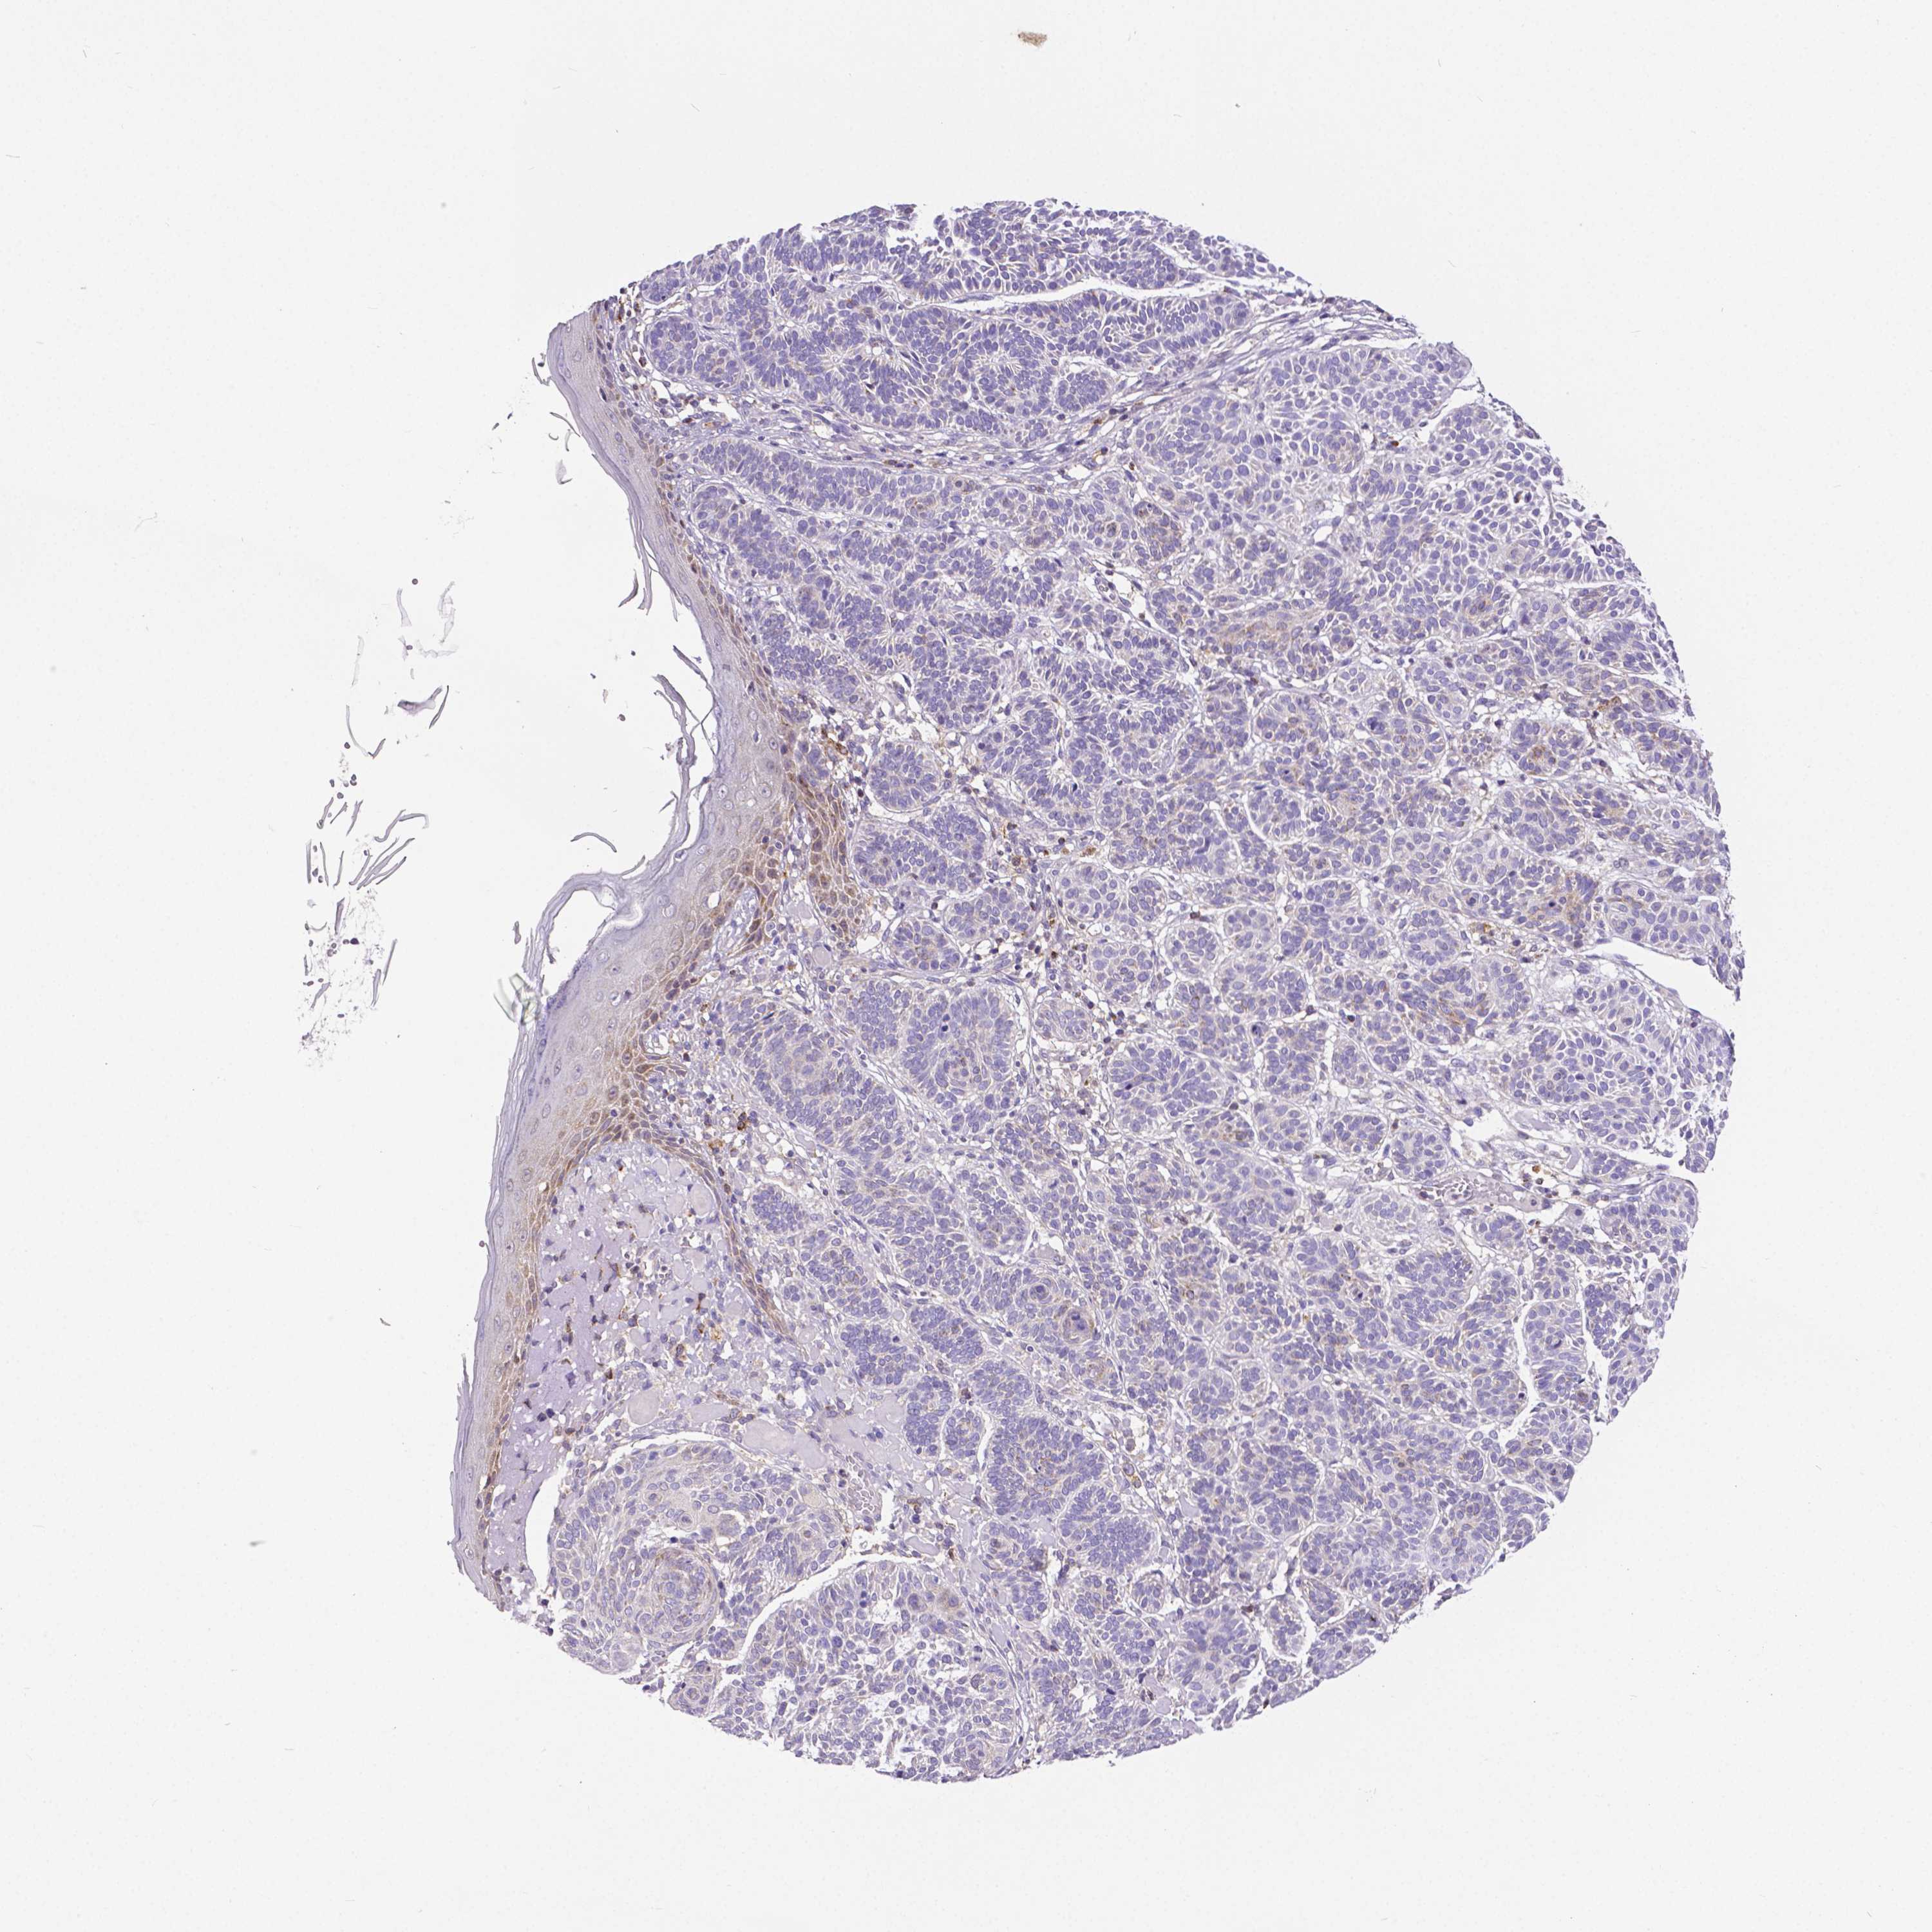

SKIN CANCER - Protein expressioni

A mouse-over function shows sample information and annotation data. Click on an image to view it in a full screen mode. Samples can be filtered based on level of antibody staining by selecting one or several of the following categories: high, medium, low and not detected. The assay and annotation is described here.

Antibody stainingi

Antibody staining in the annotated cell types in the current human tissue is reported as not detected, low, medium, or high, based on conventional immunohistochemistry profiling in selected tissues. This score is based on the combination of the staining intensity and fraction of stained cells.

Each image is clickable and will lead to virtual microscopy that enables deeper exploration of all samples and also displays staining intensity scores, fraction scores and subcellular localization as well as patient and tissue information for each sample.

Antibody HPA008455

Antibody HPA031125

Staining

High

Medium

Low

Not detected

Intensity

Strong

Moderate

Weak

Negative

Quantity

>75%

75%-25%

<25%

None

Location

Nuclear

Cytoplasmic/membranous

Cytoplasmic/membranous,nuclear

Squamous cell carcinoma, NOS

Squamous cell carcinoma, metastatic, NOS

Basal cell carcinoma

Papilloma, NOS